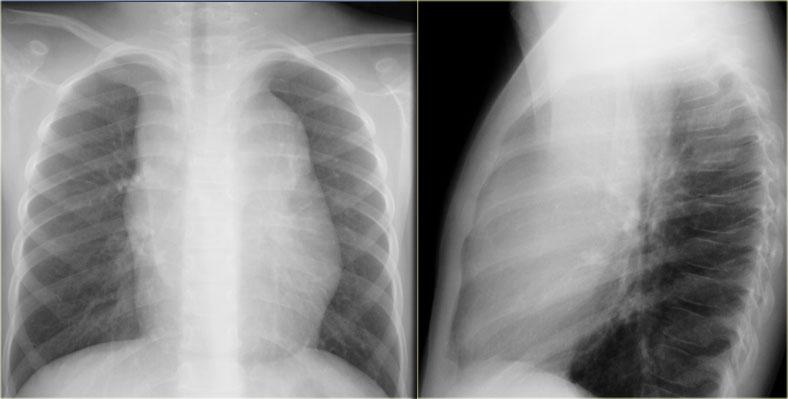

Tuyến ức phì đại có hình tứ giác với bờ bên lồi, thùy múi.

Phim ngực cho thấy các đặc điểm điển hình của u lympho Hodgkin, ví dụ: một khối trung thất trước.

Các hình ảnh CT của cùng bệnh nhân cho thấy một khối mô mềm lớn ở trung thất trước, xuất phát từ tuyến ức.

Có hạch cạnh khí quản kèm theo (mũi tên).